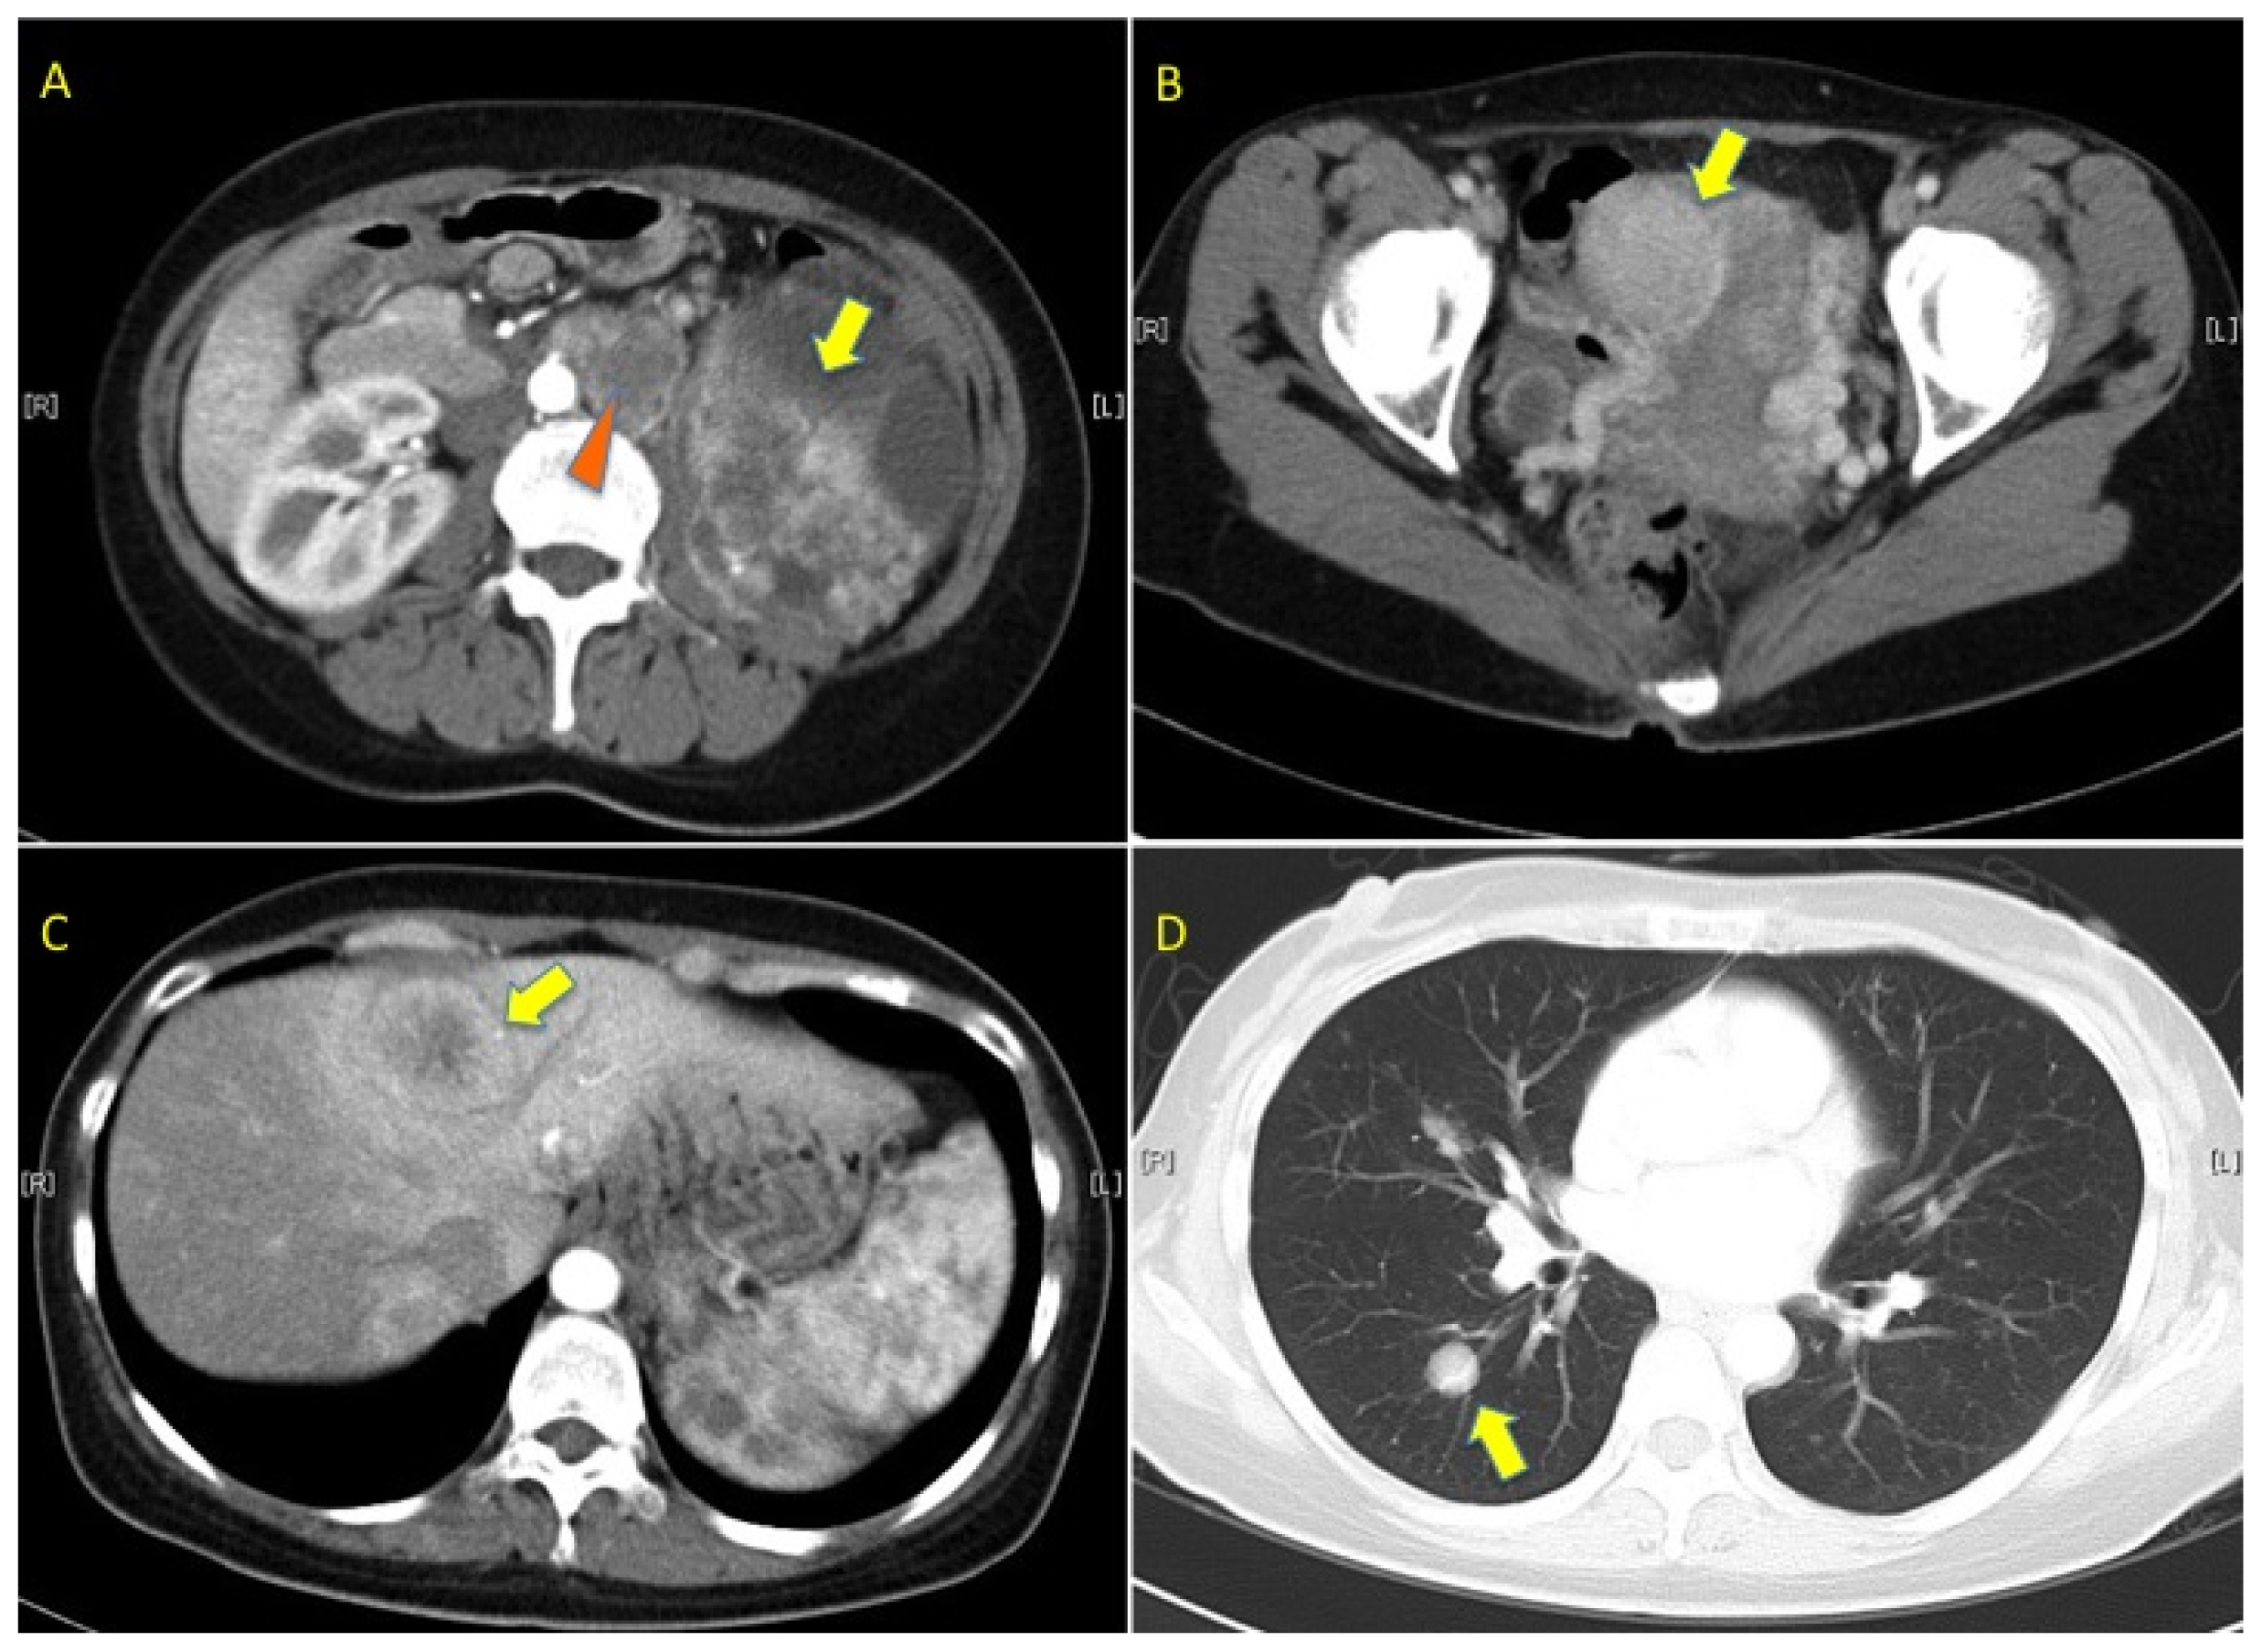

2. Case Presentation

2.1. Pedigree 1

2.2. Pedigree 2